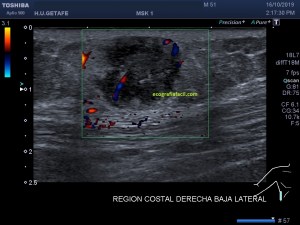

Con la eco pasa igual…cuando queremos estudiar, por ejemplo, el recto anterior del muslo en axial,perfecto…pero en longitudinal, como la imagen 2, se complica porque desde la rótula a la inserción en la cadera, tenemos mucho recorrido. En este caso hacemos lo mismo que cuando hacemos la foto del atardecer…nos ponemos en un extremo, activamos la funciona, recorremos suave y continuamente por la anatomía que queremos fotografiar y ya está…mira la pantalla y no el movimiento de tu mano,como si hicieses la foto, ves la pantalla,pero no como mueves el teléfono.

Es muy útil para lesiones que han crecido mucho y no podemos conjugar en una sola imagen, por ejemplo, un lipoma, cuando superan la medida de la huella de la sonda no son medibles, hay que usar «panoramic view», y como este caso, otros muchos.